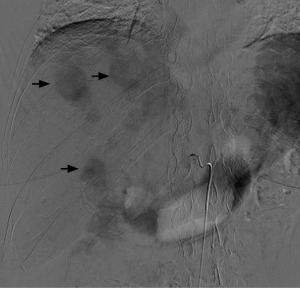

Angiographic lesion vascular grade assessment

Visual vascular grading of the lesions was performed using images obtained during diagnostic angiography. For each patient, two board-certified interventional radiologists blinded to the treatment regimen reviewed the digital subtraction angiograms. Angiographic tumor vascularity was categorized into 4 grades for each patient. We conducted our visual rating inspired by rating systems used in a study focusing on recurrent glioblastoma multiforme and anaplastic astrocytomas (10), another study utilizing digital subtraction angiography (DSA) for visual rating in gliomas (11), and research on the vascularization of liver metastases (12). The angiographic tumor vascularity of each patient was classified as follows: grade 1, avascular tumors; grade 2, mild tumor flushing; grade 3, tumor flushing with an arterial network; and grade 4, abnormal vascularization and arteriovenous shunting (Figures 1-4). Compared with the reference study (12), the lesions of patients with grade 1 and 2 tumors in our study showed similar or less contrast enhancement than the normal parenchyma, aligning with the hypovascular class in the reference. In contrast, the lesions of patients with grade 3 and 4 tumors, which exhibited a higher contrast than the surrounding hepatic parenchyma, corresponded to the hypervascular class in the reference study.